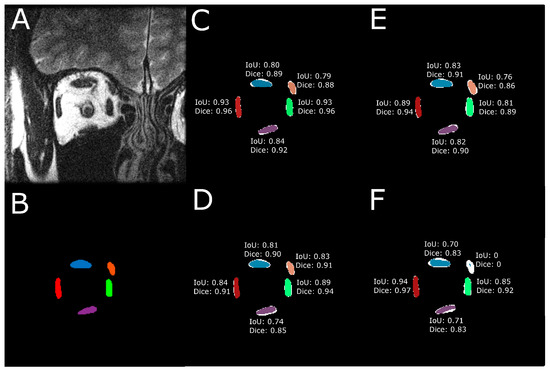

3.2. Assessment of EOM Centroid Estimation

3.6. Impact of MRI Slice Location on Estimated EOM Centroids